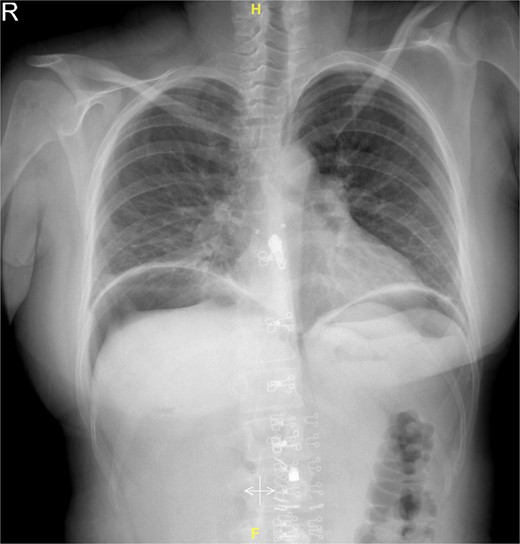

Upon examination, she had tachycardia and was tachypneic. However, the blood pressure, temperature, and oxygen saturation were within normal limit. The abdomen was soft and not distended, with mild surgical site tenderness. Surgical wound was clean and dry. Analgesia was given to the patient, but her vital signs showed no improvement. The hemoglobin (Hb) level was 9 g/dl, with the white blood cells (WBCs) count of 12 × 10%/l. Electrolytes, liver, and renal function tests were all within normal parameters. On erect chest film, there was air under the diaphragm (Fig. 1).